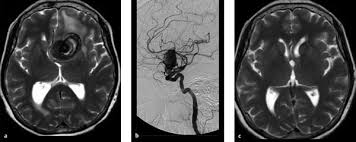

Surgical And Endovascular Treatments For Cerebral Aneurysm Download Scientific Diagram from www.researchgate.net The exact cause of an aneurysm isn't clear, but certain factors can contribute to developing one, such as high blood pressure. Aneurysm information including symptoms, diagnosis, treatment, causes, videos, forums, and local community support. For other uses, see aneurysm (disambiguation). Find answers to health issues you can trust from healthgrades.com. By contrast, false aneurysms are external hematomas with a persistent communication to a leaking artery. Aneurysm, widening of an artery that develops from a weakness or destruction of the medial layer of the blood vessel. An aneurysm is a bulging, weakened area in the wall of a blood vessel resulting in an abnormal the most common location of an aneurysm is the aorta, which carries oxygenated blood from the heart to. # перевод песни aneurysm (nirvana).

Cerebral aneurysm (aneurysm in the brain).